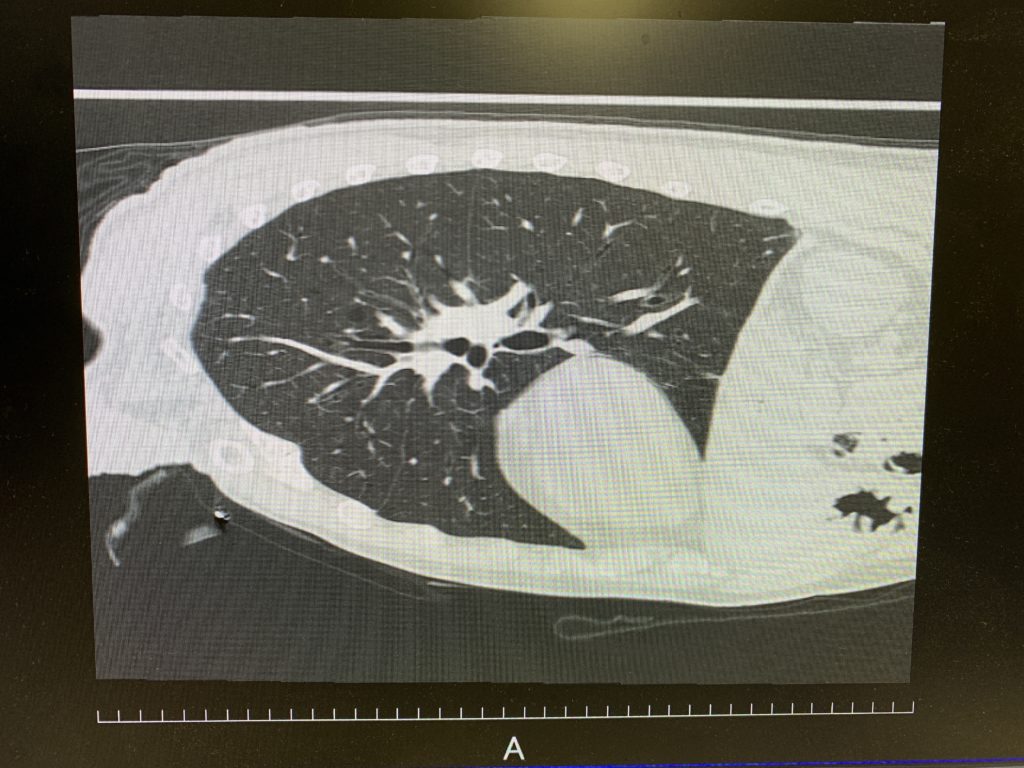

未分類 3/31 2025年3月31日 2025年3月31日 Toshi Facebook Twitter Google+ はてブ Pocket Feedly 朝から東京マーケットは下げてます。3.5%くらい? 4/2を見据えてリスクオフかな STくんの手術 肺実質を傷つけると血がでるんだよー 助手は吸引+必要に応じて止血 でいいか いい手段だなあ よくやるなあと わかってない人はいる わかってない人にどう教えるのか とりあえず 最初からpitfallの各論教えといた方がいいな 臨床 off the jobトレーニング たてみぞ横溝よくわかってない ここまでやらせよう、とか ここからはかわろう、とか Facebook Twitter Google+ はてブ Pocket Feedly